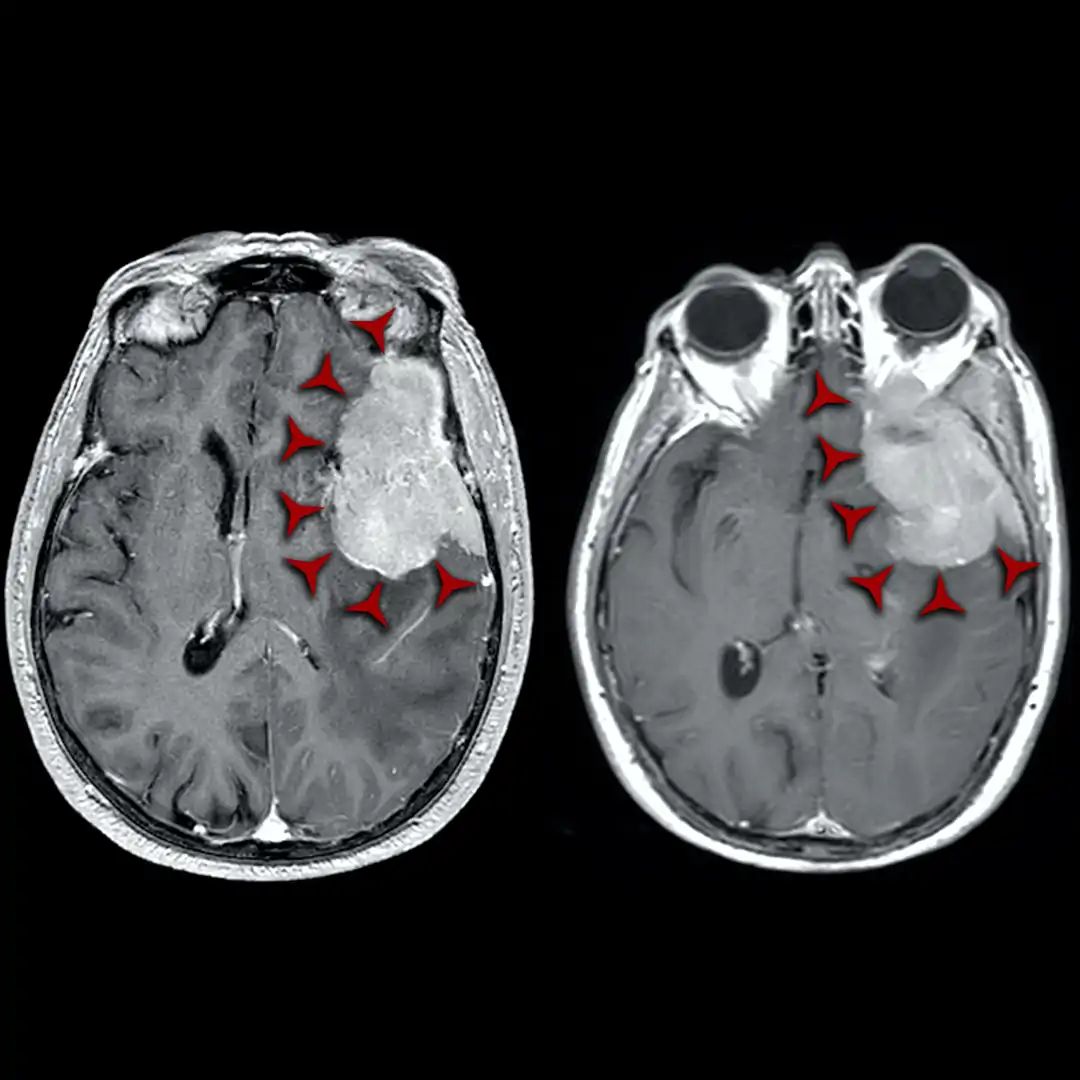

Un nuovo progetto di ricerca della AOU Città della Salute e della Scienza di Torino apre prospettive importanti nella diagnosi e nel trattamento dei meningiomi, tumori cerebrali che rappresentano circa il 40% delle neoplasie primarie intracraniche. L’iniziativa, coordinata dal professor Luca Bertero della struttura di Anatomia Patologica 2 U diretta dalla professoressa Paola Cassoni, si concentra sull’utilizzo di strumenti di diagnostica molecolare avanzata per prevedere in modo più preciso il rischio di recidiva a lungo termine e valutare il potenziale beneficio della radioterapia nei singoli pazienti.

Oggi la diagnosi si basa soprattutto sulla combinazione di dati clinici, neuroradiologici e anatomopatologici. L’analisi istologica del tessuto tumorale consente di classificare il tumore in base al grado di malignità, fornendo indicazioni per la prognosi e il percorso terapeutico. Tuttavia, questo approccio non sempre è sufficiente: tumori apparentemente simili possono evolvere in modi molto diversi, e in numerosi casi le caratteristiche istopatologiche risultano ambigue.

Immagine di repertorio

Negli ultimi anni la ricerca ha aperto nuove strade con le indagini di profilo di metilazione del DNA tumorale, capaci di migliorare la caratterizzazione dei tumori cerebrali. Questi esami, condotti sul tessuto già prelevato con la biopsia o l’intervento chirurgico, permettono una stratificazione prognostica più precisa, aiutando i medici – neurochirurghi, radioterapisti e neuro-oncologi – a scegliere la terapia più adatta.